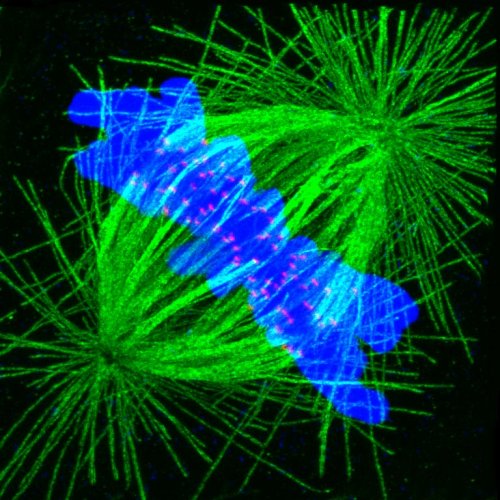

Cromosomas de una célula a punto de dividirse (en azul) organizados en la línea ecuatorial del huso mitótico (en verde), esperando el permiso por parte de mecanismos reguladores de la célula para separarse hacía los dos polos del huso y formar núcleos de 2 células hijas. (Foto: MARGEN)

Según un artículo publicado recientemente por el doctor Jan Tesarik en la revista Reproductive Biomedicine Online, los embriones humanos afectados por anomalías cromosómicas poseen mecanismos de autodefensa que les permiten detectar y bloquear las células anormales. Cuando estos mecanismos detectan una anomalía cromosómica, la división de los cromosomas, localizados en la línea ecuatorial del huso mitótico (Imagen 2) no progresa, la célula no se divide, desactiva su expresión genómica y finalmente se desintegra y desaparece. Así un embrión inicialmente portador de anomalías cromosómicas se puede convertir espontáneamente en un embrión normal.